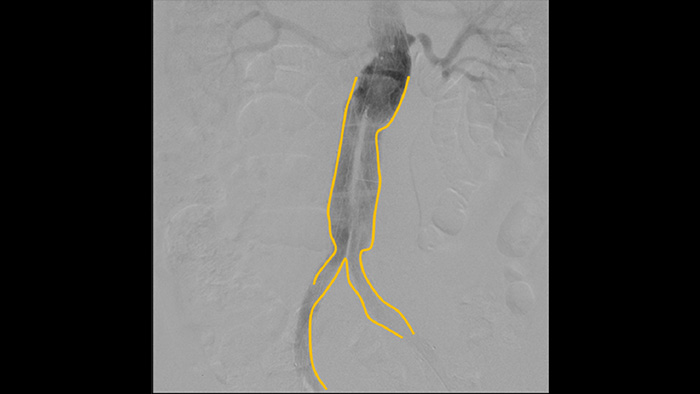

Com o arco cirúrgico portátil Zenition da Philips, o Dr. Vila está obtendo imagens de qualidade excepcional que lhe permitem realizar a maioria dos procedimentos vasculares com uma configuração de baixa dose.

Com o Zenition, nossa qualidade de imagem de ASD melhorou muito. Não vemos mais uma imagem granulada, somente uma imagem muito clara."

Dr. R. Vila, MD

Hospital Universitário de Bellvitge, Barcelona, Espanha

A angiografia por subtração digital (ASD) é usada em procedimentos vasculares intervencionistas para visualizar os vasos sanguíneos com clareza, removendo estruturas que podem obscurecer a visibilidade dos vasos. A fluoroscopia do roteiro sobrepõe uma imagem com contraste subtraída adquirida anteriormente à fluoroscopia ao vivo, permitindo que você monitore um dispositivo sem reinjetar contraste.

Use a ferramenta Contorno para marcar com facilidade uma bifurcação ou ramos laterais, simplesmente desenhando no monitor da Estação de Visualização Portátil com o dedo ou um mouse conectado externamente.